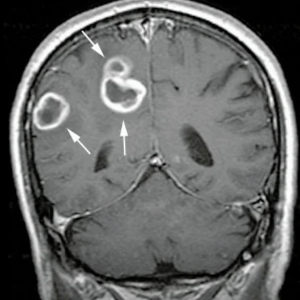

শিশুদের ক্যান্সার